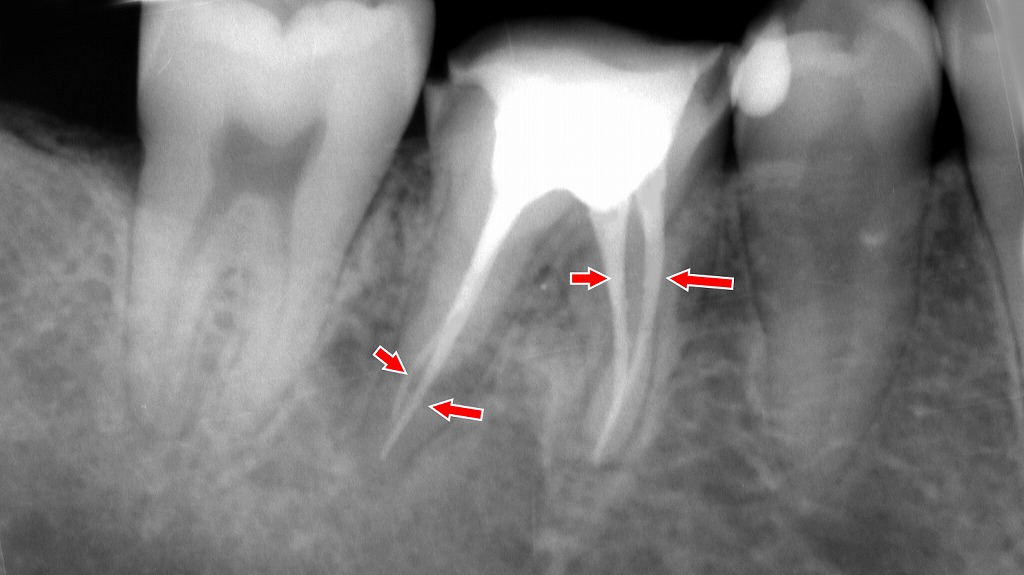

下顎6番は遠心に深い虫歯が進行し、歯髄が細菌感染した結果、根尖部には透過像として根尖病巣が認められました。そのため、感染した歯髄を除去し根管内を清掃・消毒する抜髄処置を行い、4根管すべてに対して根尖まで適切に根管充填を行いました。レントゲンでは各根管に充填材が連続的に満たされ、根尖まで良好に封鎖されていることが確認できます。これにより再感染のリスクを抑え、歯の保存が可能な状態へと整えられています。